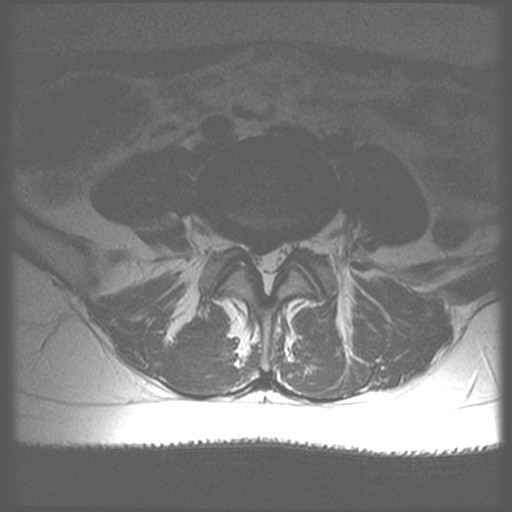

Centrale Wervel Zuil